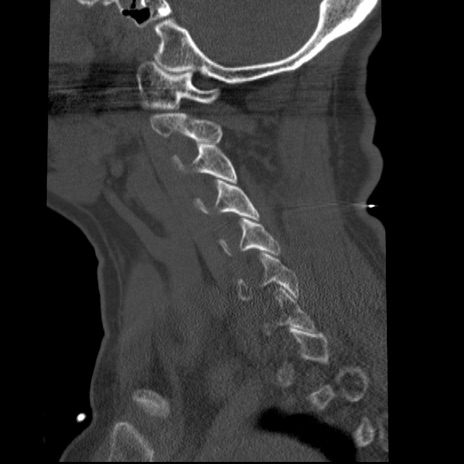

症例50 頚椎CT(矢状断像)

【症例】60歳代女性

【主訴】後頭部〜右後頸部にかけての痛み

【現病歴】本日飲食店でコーヒーを飲んでいたところ、突然後頭部〜右後頸部にかけて痛みが出現し、右上肢の感覚障害を伴ったため救急要請。

【身体所見】脳神経学的に明らかな異常所見を認めず。右上肢に軽度の感覚障害あり。

異常所見と診断は?

頚椎CT